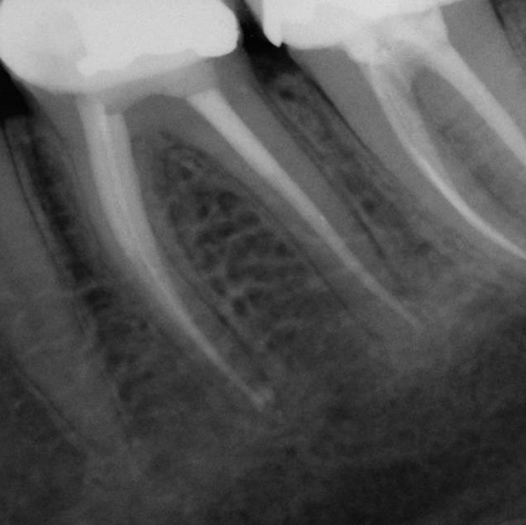

Before

Before Root Canal treatment